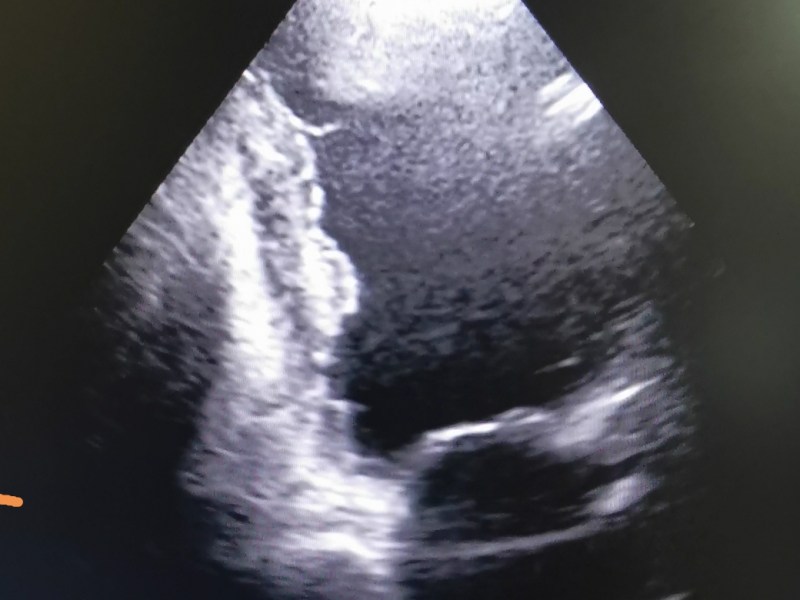

Trombul intracardiac

Tromb (cheag) cardiac, apărut prin perturbarea circulației intracardiace a sângelui, în acest caz prin contracție deficitara a muschiului cardiac cu scăderea forței de…